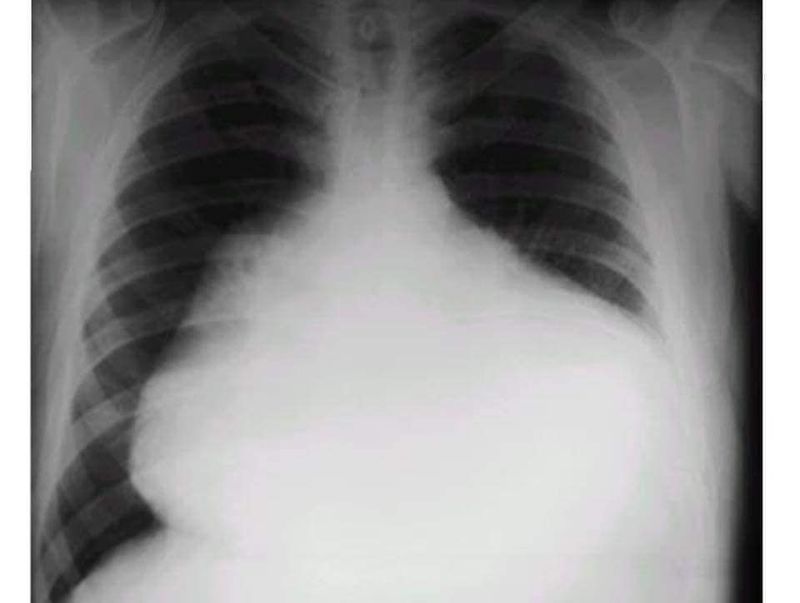

The water bottle sign or configuration refers to the shape of the cardiac silhouette on erect frontal chest x-rays in patients who have a very large pericardial effusion. Typically the effusion has accumulated over many weeks to months (e.g. in patients with malignancy) and the pericardium has gradually stretched. The fluid, often measuring a liter or more, causes the pericardium to sag, mimicking an old-fashioned water bottle sitting on the bench. This sign is seen in Pericardial effusion ("fluid around the heart") which is an abnormal accumulation of fluid in the pericardial cavity. Because of the limited amount of space in the pericardial cavity, fluid accumulation leads to an increased intrapericardial pressure which can negatively affect heart function.